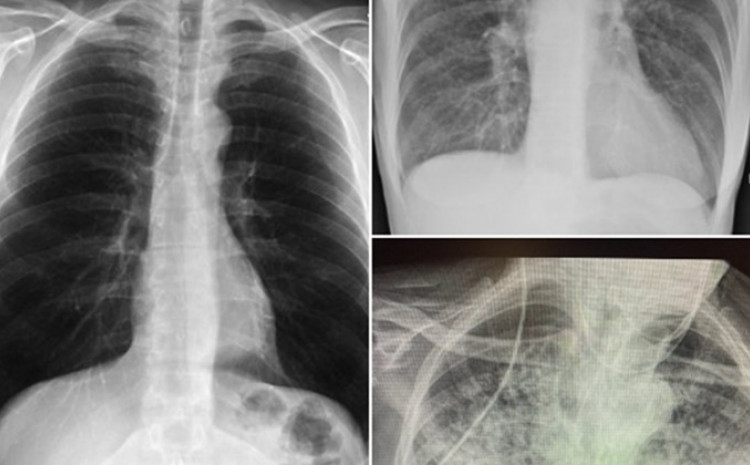

Naime, ona je na svom Twitter profilu podijelila tri rendgenske snimke pluća: jednog zdravog pacijenta, jednog pušača i jednog pacijenta koji je prebolio koronavirus.

Rendgenski snimci

- Ne znam tko ovo treba vidjeti, ali pluća nakon Covida izgledaju gore od bilo koje vrste pluća pušača koju smo ikad vidjeli. I ona se urušavaju. I zgrušavaju. I otežano disanje se zadržava... i dalje ... i dalje - napisala je uz rendgenske snimke.

Snimka pluća zdravog pacijenta je bistra jer imaju puno crnog prostora, što ukazuje na to da osoba može udahnuti puno zraka. Gledajući rendgen pluća pušača, primjetna je maglovitost koja ukazuje na ožiljke i začepljenja. Treća slika prikazuje pluća nakon Covida, koja izgledaju gotovo potpuno bijelo, što znači da su pluća ozbiljno oštećena. Nakon što je njezin tvit dobio puno pažnje i hiljade odgovora, doktorica je pozvana da kaže nekoliko riječi u vijestima na CBS-u.